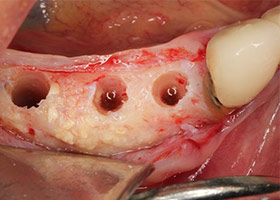

9.完成補骨手術後的健康牙床。

10.植入人工牙根於健康的牙床。

11.配合手術導引板,精準植入理想位置。

12.完成一階段式手術。